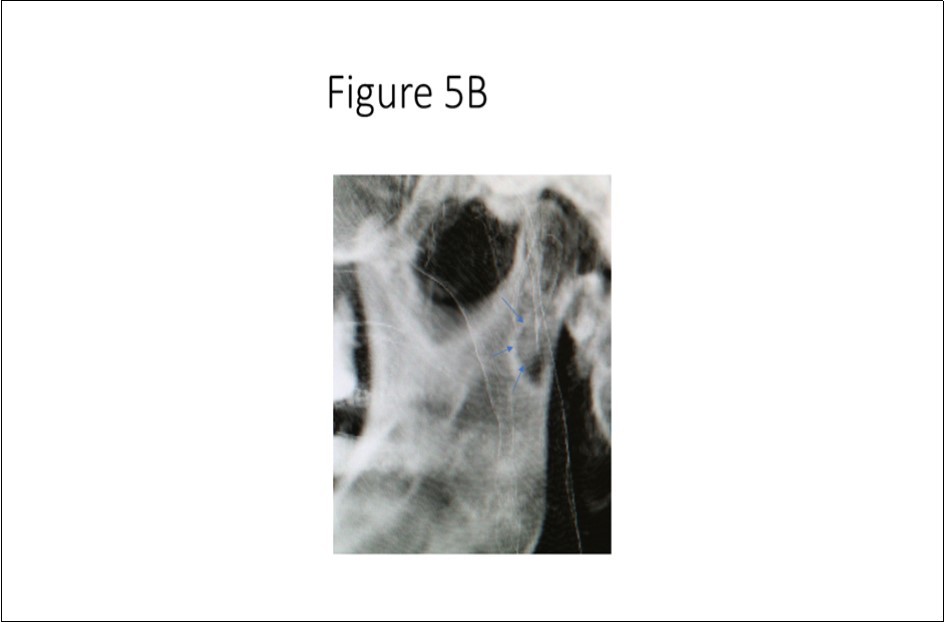

Maxillofacial examination was unremarkable. No facial swelling, masses or asymmetry was observed. The TMJ examination was normal. No pain or tenderness to digital palpation was observed in the right preauricular region. Oral examination of the patient was unremarkable. No trismus was observed as the maximal interincisive opening was greater than 40.0mm. No anterior or posterior open bite was observed. Imagining studies to rule-out intraosseous neoplastic lesions and arrive at a definitive diagnosis consisted of a panoramic radiograph and cone beam CT scan (120 kVp, 5 mA, 7.4 sec). Panoramic radiograph revealed a unilocular, well-circumscribed radiolucency in the right subcondyalar region of the mandible that was close to the posterior border of the condylar neck (Figure 2). Cone beam CT scan (i-CAT FLX, Imaging Sciences, Hatfield, PA) imaging revealed a well-defined unilocular, elliptical shaped radiolucent lesion on the medial surface of the right subcondylar neck of the mandible (Figure 3, Figure 4, Figure 5). The elliptical shaped unilocular lesion involved almost the entire horizontal dimension of the subcondylar neck (Figure 4). Figure 5 shows the three-dimensional CT scan reconstruction (i-CAT FLX, Imaging Sciences, Hatfield, PA) of the medial defect in the subcondylar region of the mandible. Based on knowledge of clinical head and neck anatomy and imaging studies, no treatment was indicated as the diagnosis was consistent with a variant of a Stafne bone cavity of the right subcondylar neck near the parotid gland and not a pathological condition. The patient was informed about the risk of condylar neck fracture due to the critical size of the SBC.

Figure 5B.Three-dimensional cone beam CT scan close up view of osseous defect on medial cortex of right subcondylar neck of mandible.